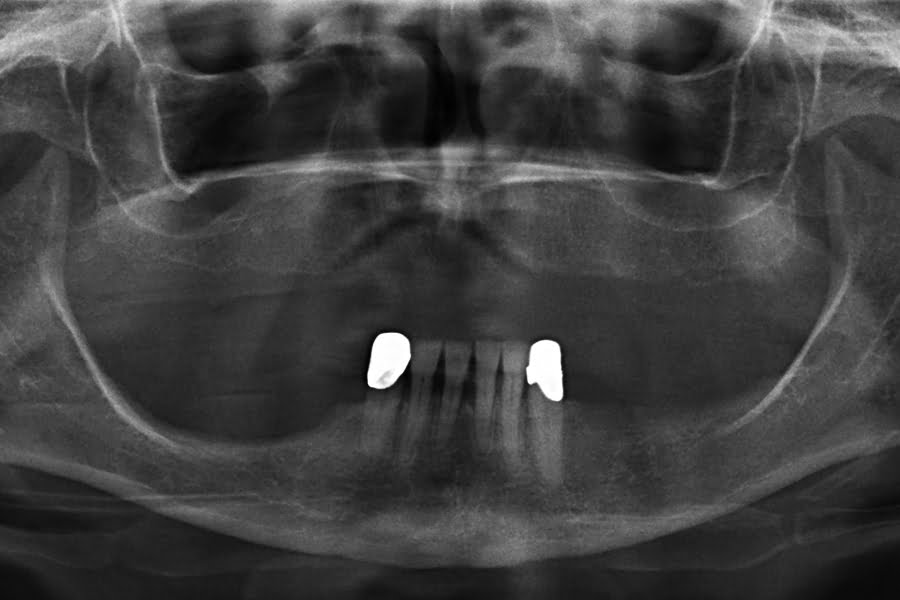

Quatro dos seis implantes foram de 5,5 mm de comprimento por 5 mm de diâmetro, um implante foi de 6,5 mm de comprimento por 3,75 mm de diâmetro e o último implante foi de 6,5 mm de comprimento por 5 mm de diâmetro (figura 2).

As seguintes imagens apresentam um dos casos incluídos no estudo (figura 03 – 15).